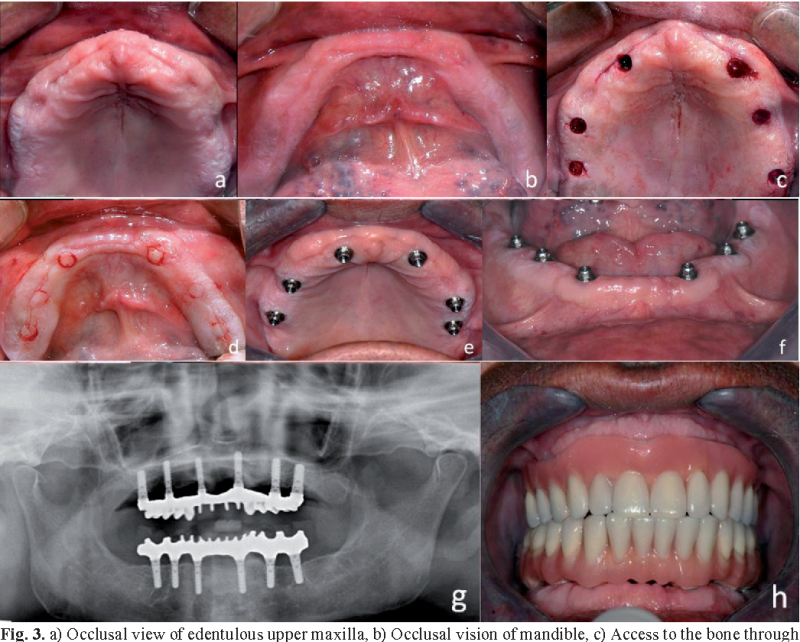

موفقیت ایمپلنت در فک پایین و فلپ فیبولا

موفقیت ایمپلنت در پیوند فیبولا 2/89 درصد و موفقیت در فک پایین تحت تابش 18/87 درصد با استفاده از اکسیژن درمانی هایپرباریک بود